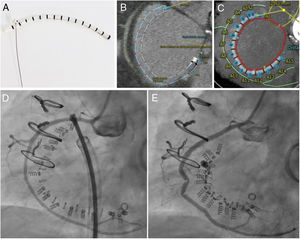

The Cardioband consists of a Dacron band that is fixed along the tricuspid annulus with a series of anchors (stainless steel screws). Inside the band there is a wire that can be adjusted, in a cinching motion, to reduce the tricuspid annulus (figure 1A). To determine whether the patient's anatomy is suitable for the implant, in addition to echocardiography, it is essential to perform cardiac computed tomography. The size of the implant is chosen based on the length of the annulus, measured from the start of the anterior leaflet to the coronary sinus; the distance to the right coronary artery must also be assessed, to avoid potential complications. In this case, the length measured on computed tomography was 105.6 mm, which corresponded to a size E Cardioband (there are 6 sizes), with no a priori risk of coronary perforation (figure 1B, C).

A: images of the Cardioband, which consists of a Dacron band with radio-opaque markers and an internal wire. B and C: 3mensio computed tomography reconstruction (Pie Medical Imaging; Maastricht, Netherlands), showing the length of the Cardioband along the tricuspid annulus (red), the anchors (blue), the distance to the right coronary artery (green) and the distance to the aortic valve (yellow) from the first screw in the implant. D: images of the Cardioband and the right coronary artery immediately after implantation before adjustment. E: Cardioband after adjustment and reduction of the annulus, with evidence of traction on the right coronary artery.

The procedure was performed under general anesthetic and with fluoroscopic and transesophageal echocardiographic guidance. The left femoral artery was cannulated for right coronary artery catheterization with a guide catheter, and an angioplasty guidewire was inserted as a marker of the tricuspid annulus. Via right femoral venous access, a 24 Fr steerable sheath from the Cardioband deployment system was introduced into the right atrium. Through this, a guide catheter was advanced to the site of attachment of the band, containing the implant catheter that deploys the anchors to fix the band to the tricuspid annulus. The implant was attached starting at the anteroseptal commissure, 25 mm from the aortic valve, and running clockwise to the posteroseptal commissure. As the guide catheter was withdrawn to expose the Dacron band, the band was fixed to the annulus with 16 screws: 3 within the first 10mm and then 1 every 8mm. Once implanted, the guide catheter and implant catheter were withdrawn and a separate catheter was introduced to adjust the size of the implant, reducing the septolateral diameter of the tricuspid annulus by cinching the wire inside the Cardioband, from 50 to 36 mm on echocardiography. After the annulus had been adjusted, 2 stenoses were observed in the middle segment of the right coronary artery, probably caused by the traction exerted, the long-term significance of which is unknown (). At the end of the procedure, the patient had moderate TR (figure 2, ). She was discharged 2 days later having improved clinically and functionally (New York Heart Association functional class II); at 1-month postdischarge she had no signs of right heart failure.